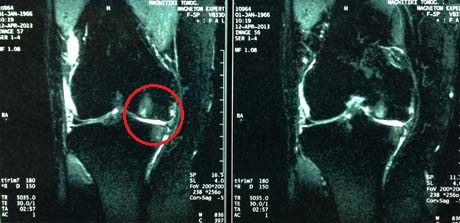

Η μαγνητική τομογραφία αναδεικνύει τη βλάβη του αρθρικού χόνδρου καθώς και την κατάσταση των μηνίσκων και των μαλακών μορίων